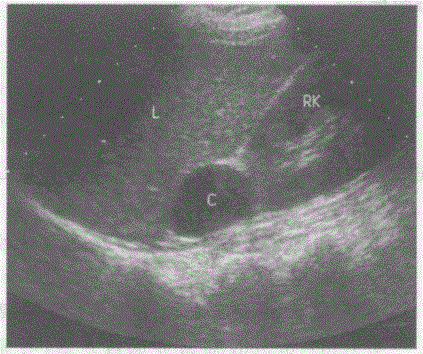

问题 临床资料:女,50岁,常规体检。 超声综合描述:肝右叶、右肾之间可见3.1cm×2.4cm椭圆形无回声区,内透声清亮,边界清晰,壁薄光滑,后方声加强。 超声提示:

选项 A.右肾上极囊肿 B.肝右叶囊肿 C.右肾上腺囊肿 D.右肾上腺神经母细胞瘤

答案 C